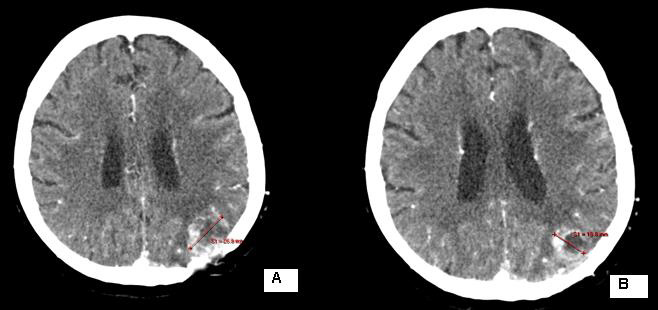

Due to seizure symptoms 2 weeks after RT, the irradiated relapse (Figure 7/B) was operated and histologically confirmed as necrotic brain tissue.

Figure 7: CT of the second local recurrence: A / before the local RT; B / Over 50% reduction of tumor volume after local RT up to TD 45 Gy with DD 1.8 Gy.